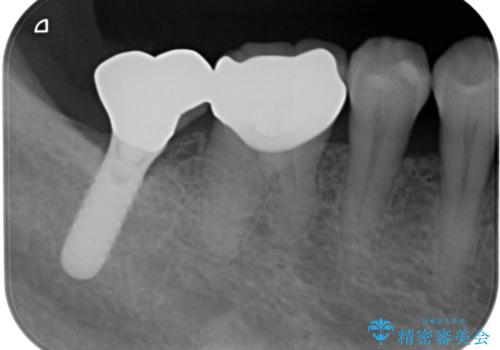

不適合だった詰め物の裏側に大きな虫歯がありました。

セラミックインレーやアンレーでは強度に不安が残るため、クラウンでの修復処置としました。